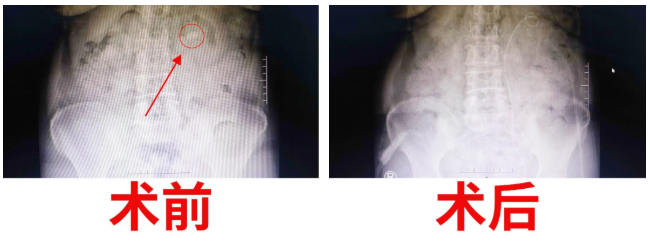

經(jīng)過(guò)泌尿外科醫(yī)護(hù)人員的密切觀察和精心護(hù)理,手術(shù)后的第三天,復(fù)查X光片,發(fā)現(xiàn)腎結(jié)石已消失得無(wú)影無(wú)蹤?!坝辛诉@樣先進(jìn)的機(jī)器,以及泌尿外科醫(yī)生團(tuán)隊(duì)高超的技術(shù),我們腎結(jié)石患者再也不用受病痛之苦了,這真是我們廣大腎結(jié)石患者的福音啊?!被颊呒?dòng)的連聲道謝。一周后康復(fù)出院。